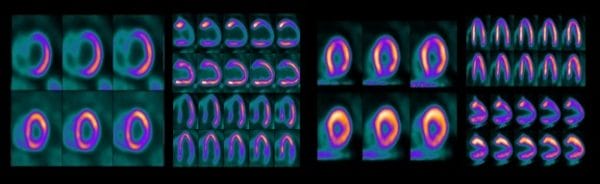

CARDIOLOGY, biograph mCT delivers a fast and reproducible cardiology workflow. Digital LSO-based detectors enable routine use of short-lived isotopes for cardiac imaging. Cardiac dedicated features deliver automated PET and CT data registration and fast reconstruction of dynamic datasets simultaneously with acquisition.

All photographs and data are a courtesy of Siemens Healthcare GmbH.